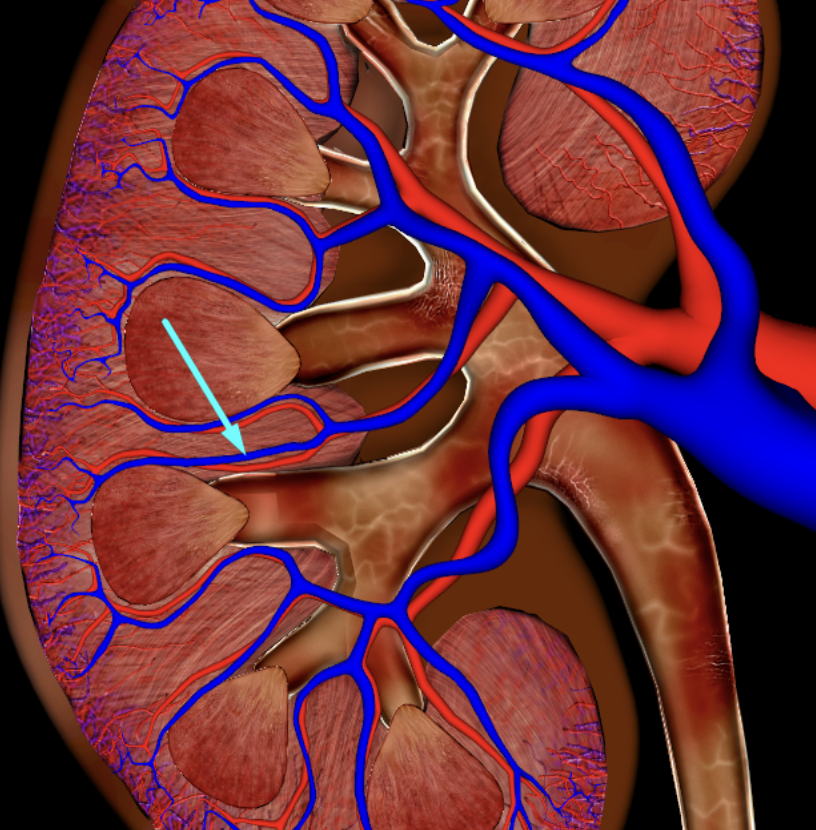

afferent arteriole

yellow

glomerulus

green

efferent arteriole

purple

orange: peritubular capillaries

green: vasa recta

efferent arteriole give rise to orange and green

interlobular vein

segmental artery

interlobar vein

arcuate artery